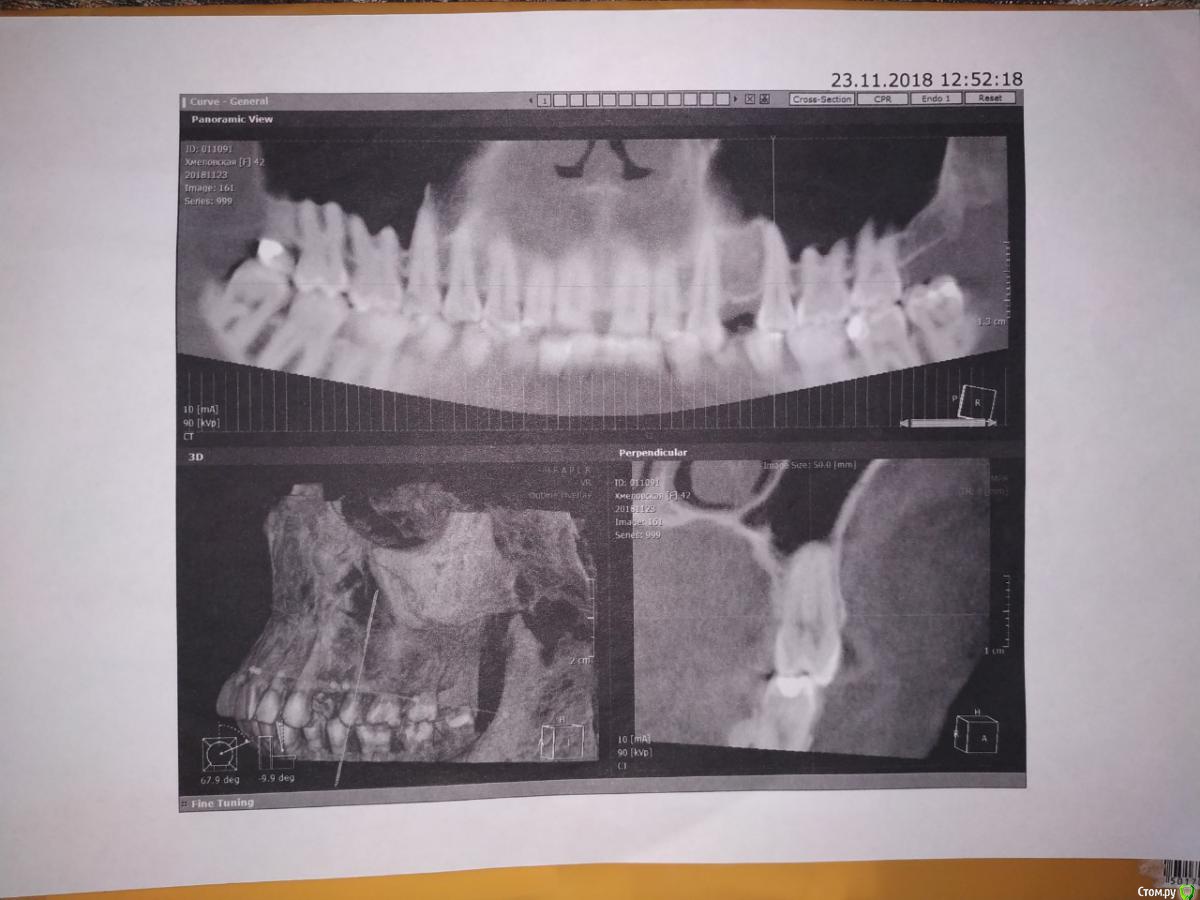

В июле  было подтекание между 6 и 7 зубом. как будто водичка. Ничего особенного но вызывало определенный дискомфорт.  Изредка поднывало. Была забитость носа с левой стороны. Сделала томограмму все впорядке гайморита нет. Отек есть. походила на кукушку. Слизь отходит но не проходит. Выписали противоаллергические лекарства и назонекс в нос. Вроде стало лучше, но забитость носа осталась. Капала сосудосуживающие.

В ноябре стало побаливать ухо. И болеть нос и  как бы небо с левой стороны. Над тремя зубами. Где то внутри. Подтекание между зубами стало каждый день очень кислое. Пошла в челюстно-лицевое отделение. Сделали томограмму. Снимок зубов. здорова. Ни кист, ничего нет. Боль странная то ноющая. то отдает в ухо. То проходит. С утра просыпаюсь как правило не болит. Открываю широко рот болит где то внутри. Ощущение что там где 6 верху что то нарывает,пульсирует и дергает. Небольшая припухлость десны где 6 и 7. Определили что звук издает зуб при нажатии -6 . Послали к лору и невропатологу и парадантологу. Невропатолог-здорова.

Парадантолог сказал с карманами все впорядке. Выписала Метровиол и попить линкомицин месяц. Витамины, кальций. Сделали чистку зубов. Визуально здорова. Проверили живы ли зубы.Все  зубы отреагировали. Зубы живые. Проверяли по ощущению как бы током. Парадантолог отправила к хирургу чтобы я заказала ночную капу и снизила ночную нагрузку на зубы. В 2010 году  долго лечили 4 тоже слева. с 2008 года. Потом вырвали сказали нужно остеомиелит. И до сегодняшнего времени ничего не болело. Болит какой то корень(как бы пульсирует) и болит уже нос. На снимке пазухи чистые.

Тянет как бы небо там где корни в положении лежа. Неприятно. 5,6,7 все корни заходят в пазуху.